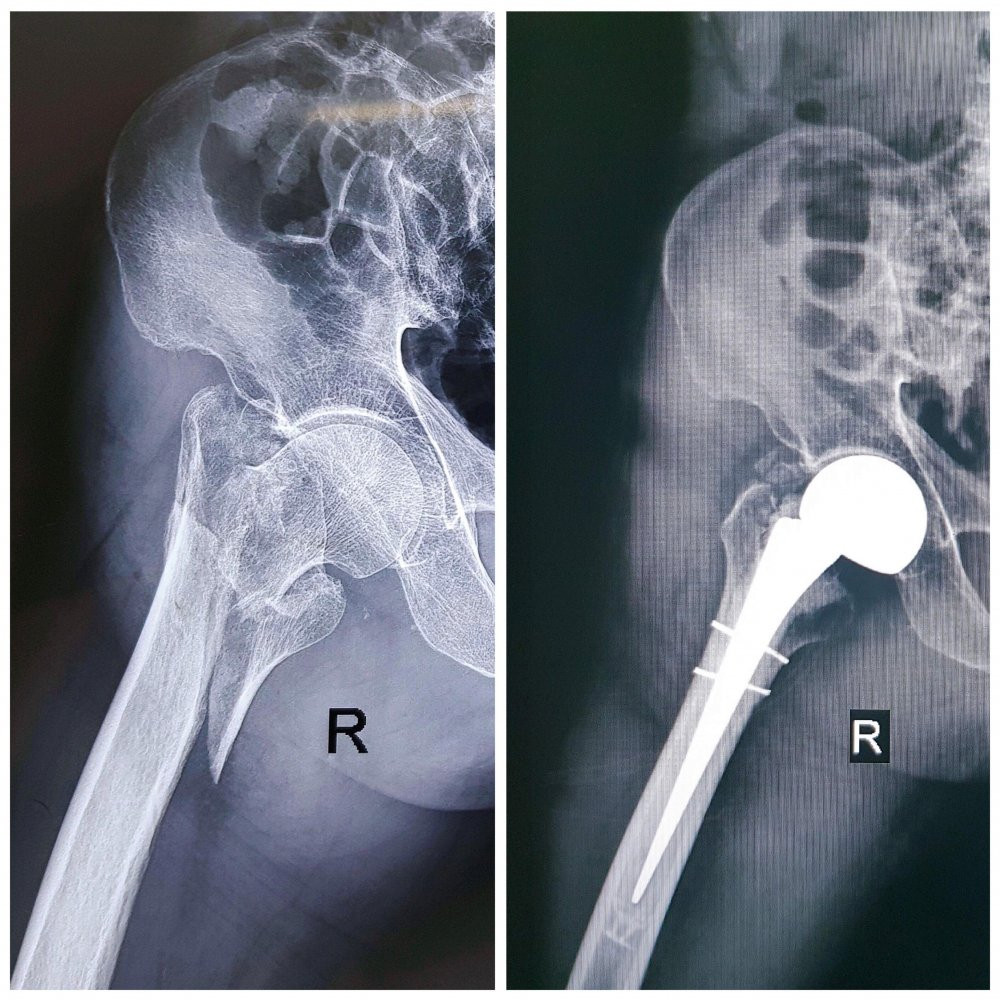

Hình ảnh xương đùi bệnh nhân trước và sau khi phẫu thuật. (Ảnh: Bệnh viện cung cấp)

Bác sĩ chẩn đoán, ông T. gãy kín liên mấu chuyển xương đùi phải và được chỉ định truyền dịch, giảm đau, phẫu thuật thay khớp háng bán phần với đường mổ nhỏ.

Hiện tại, sau 2 ngày phẫu thuật, bệnh nhân có thể ngồi dậy, bớt đau nhức. Dự kiến bệnh nhân có thể xuất viện sau 10 – 15 ngày tới.